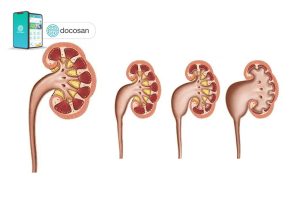

Thận ứ nước độ 4 là gì?

Bệnh thận ứ nước được chia làm 4 mức độ chính, trong đó bệnh thận ứ nước độ 4 là giai đoạn nghiêm trọng nhất của bệnh. Khi đó, nước ứ đọng trong thận thời gian dài khiến cho thận dãn nở quá mức, sưng to và biến dạng. Do đó có thể dẫn đến các biến chứng nguy hiểm như tổn thương thận, mất chức năng thận, vỡ thận. Điều này khiến bệnh nhân phải chịu những cơn đau dữ dỗi mỗi ngày, không những thế thận ứ nước độ 4 có thể ảnh hưởng đến tính mạng của người bệnh.

Thận ứ nước độ 4 xuất hiện sự giãn nở của đài thận là rất lớn, có thể lên đến trên 20mm với biểu hiện đau phần hông lưng nghiêm trọng và thường là than phiên chính của bệnh nhân khi nhập viện. Để xác định chính xác xem bạn có đang bị thận ứ nước không và bệnh đang ở mức độ nào, một số xét nghiệm cần phải thực hiện bao gồm: xét nghiệm nước tiểu, xét nghiệm máu và chẩn đoán thông qua hình ảnh chụp CT, X-quang.